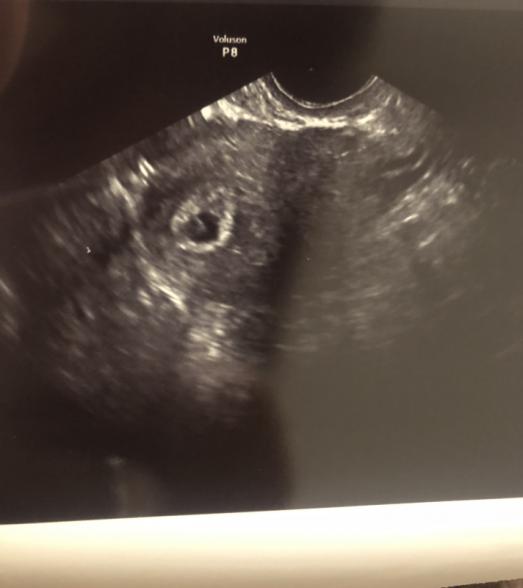

6w6d 胎嚢8.8mm 卵黄嚢と胎芽確認(サイズ不明)

・また、6w6dの際のエコーですが胎嚢周りの絨毛膜?がかなり分厚いのですが中の黒い部分でサイズを測っていました。計り方はこれが一般的でしょうか?

測り方は書いてくださったように黒い部分のサイズを測るので良いと思いますよ。